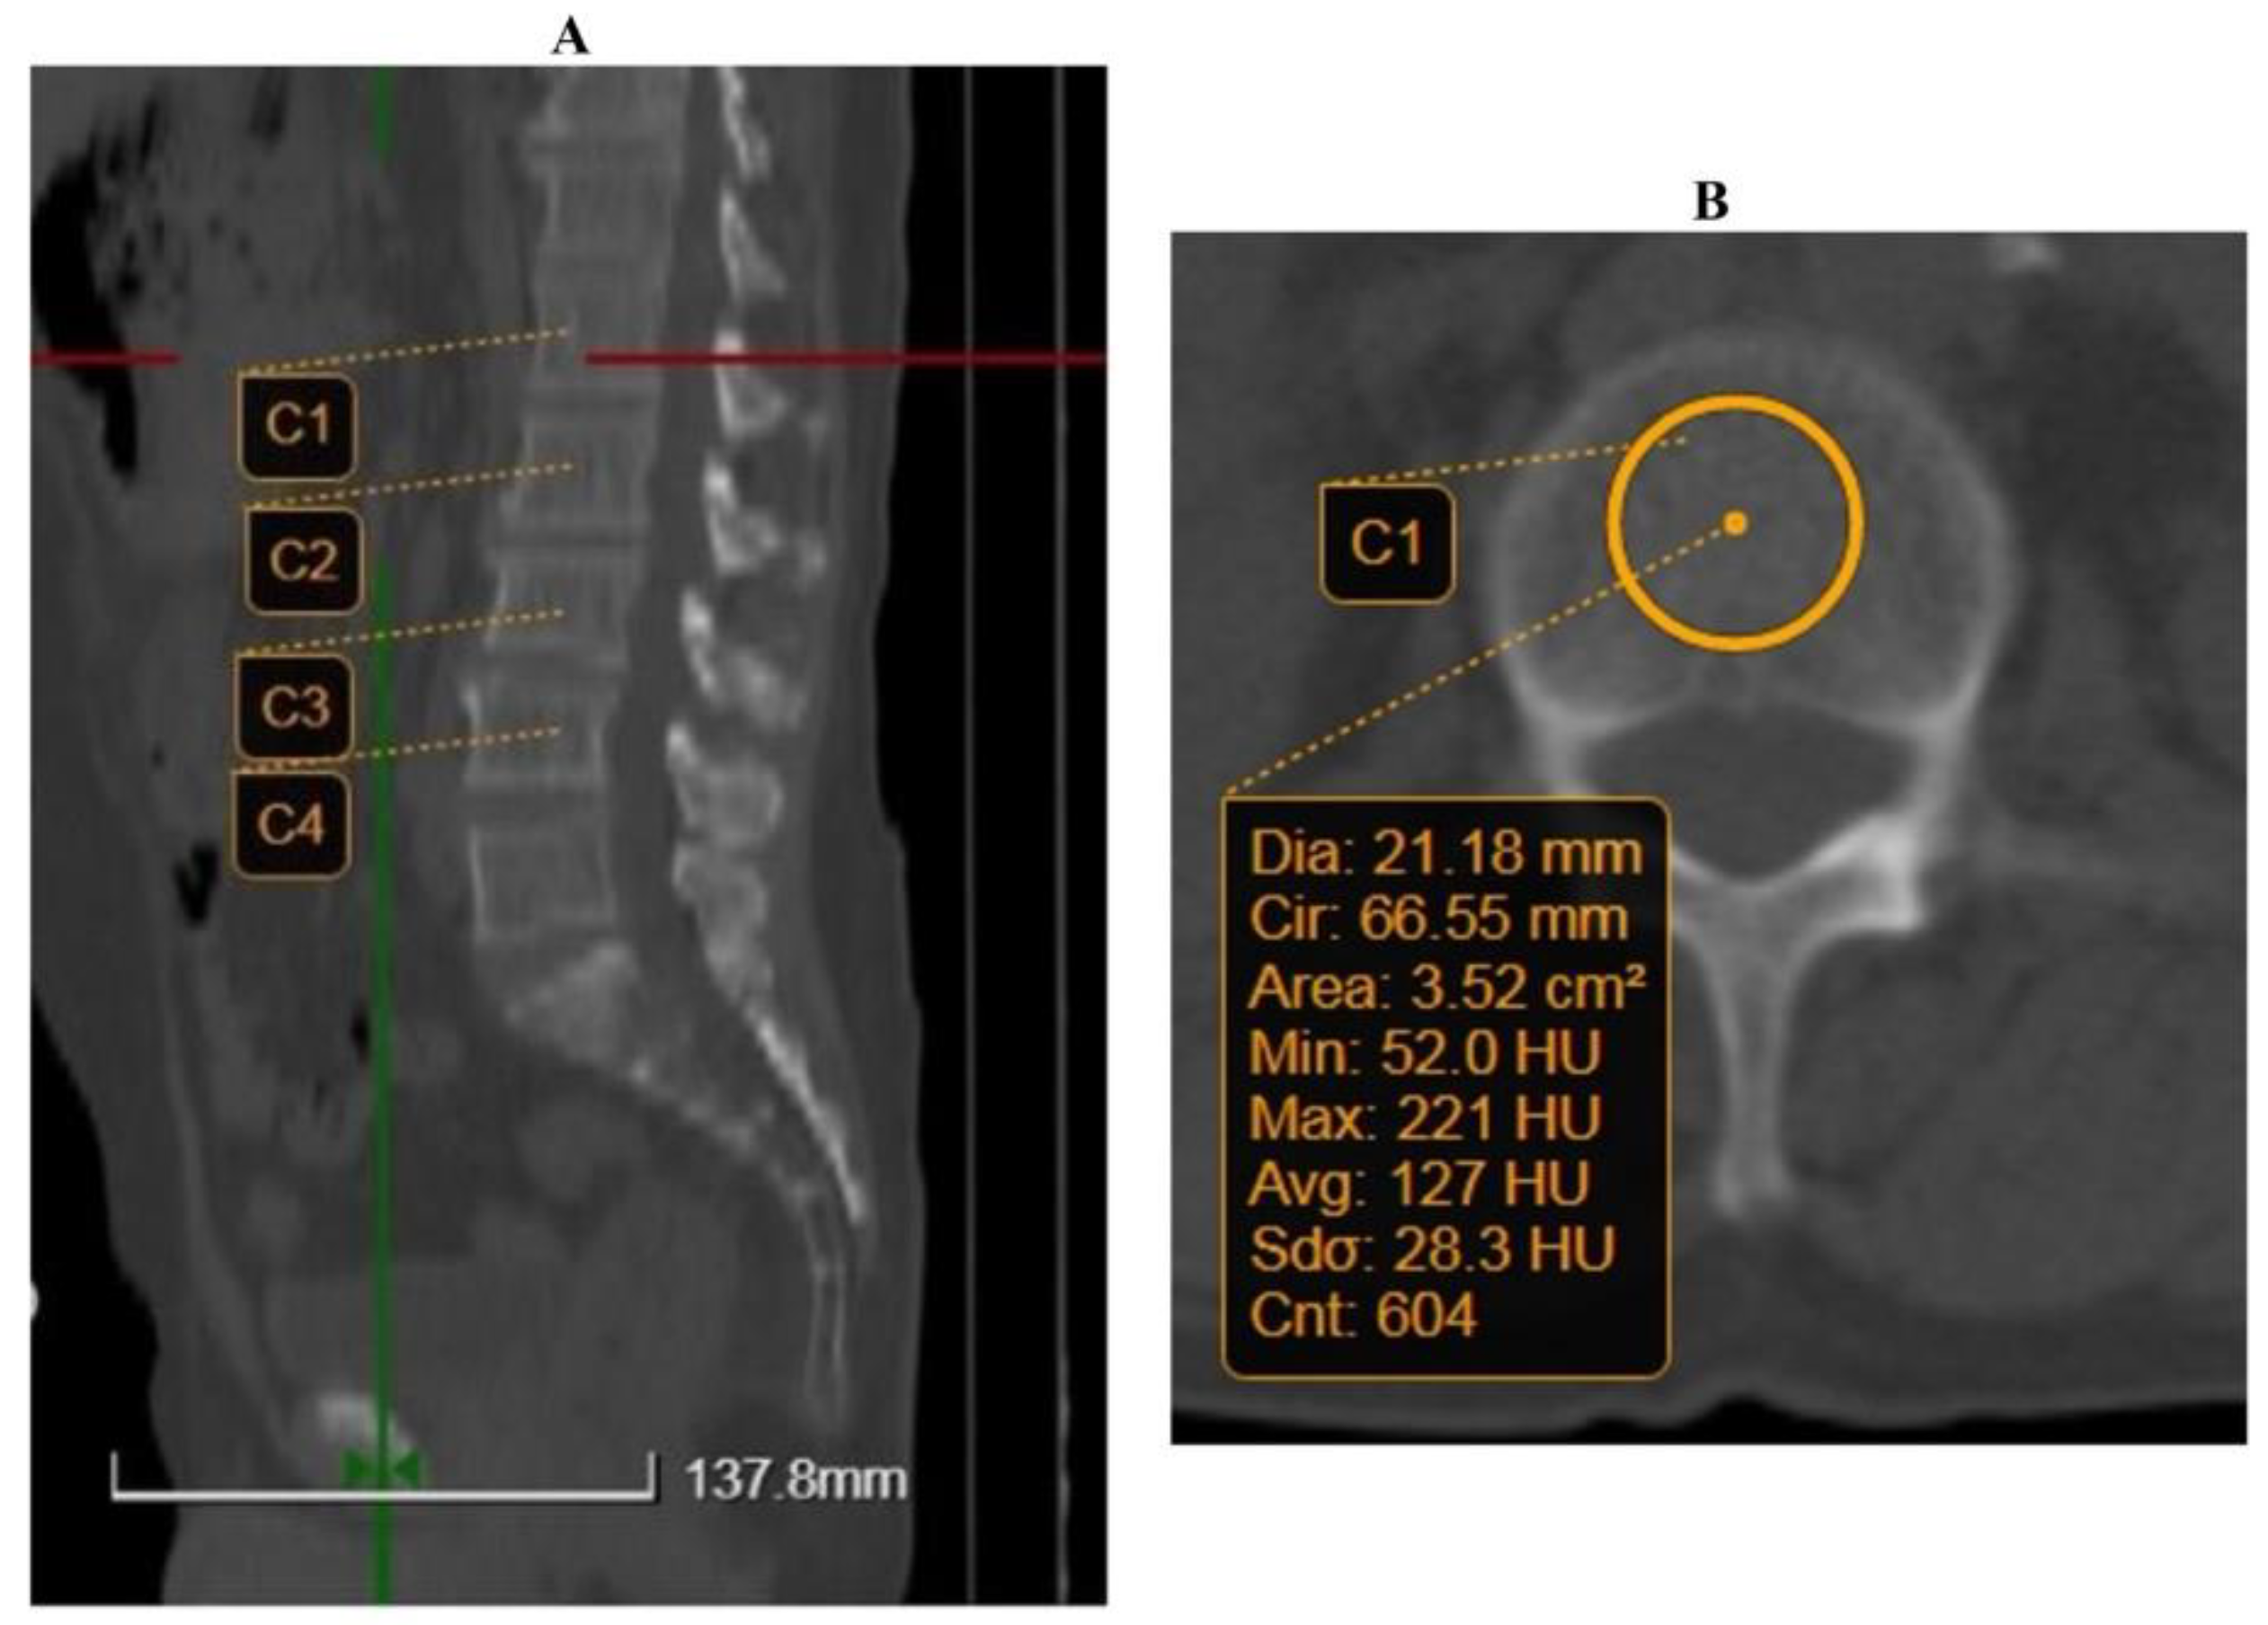

2.2. Imaging